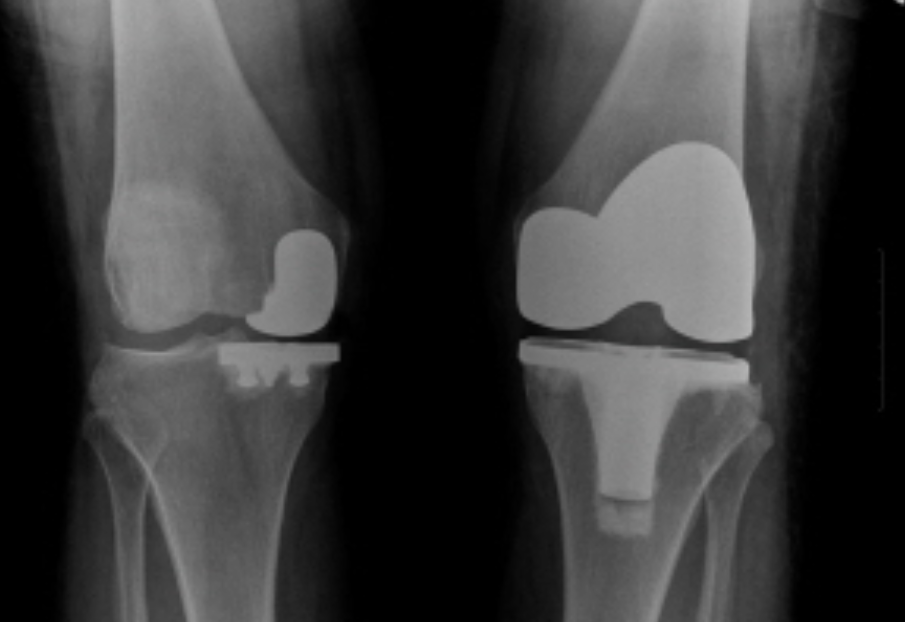

⚙️ 고관절 수술의 주요 종류

고관절 수술은 환자의 상태, 질환의 종류, 골절의 위치와 심각성에 따라 다양한 방법이 있습니다. 가장 대표적인 몇 가지 수술을 소개해 드릴게요.

3. 골 접합술 (Internal Fixation for fractures)

골절된 뼈 조각을 원래 위치로 맞춘 후 금속 나사나 판을 이용해 고정하는 수술입니다. 주로 젊은 환자의 고관절 골절이나 골두의 괴사 없이 골절만 발생한 경우에 시행하여 자신의 관절을 보존하는 것을 목표로 합니다. 뼈가 잘 붙는 것이 중요하며, 유합 기간 동안 체중 부하를 제한해야 합니다.